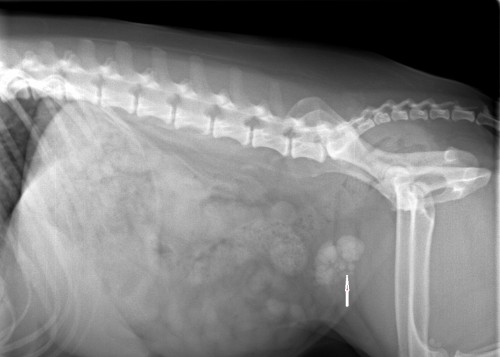

Before Surgery (arrow shows stones)